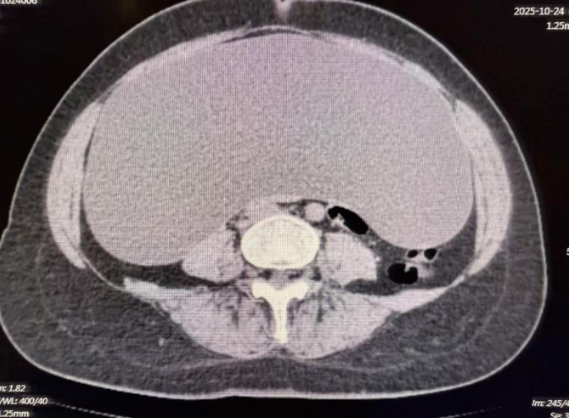

患者因发现腹腔内巨大占位性病变来到济南南郊医院就诊。术前的影像学检查结果令人震惊:腹腔内可见一范围约45cm×35cm×14cm的巨大囊性低密度影,几乎填满了整个腹腔空间,对周围脏器形成了明显的压迫。如此巨大的囊肿,不仅给患者带来了沉重的生理负担和心理压力,也对手术团队提出了极高的技术要求——如何在有限的操作空间内安全、完整地切除囊肿,同时避免损伤周围重要组织和血管,是摆在医生面前的首要难题。